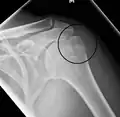

A fracture of the greater tuberosity as seen on AP X ray -

A fracture of the greater tuberosity of the humerus -

Fracture of the greater tuberosity of the humerus -